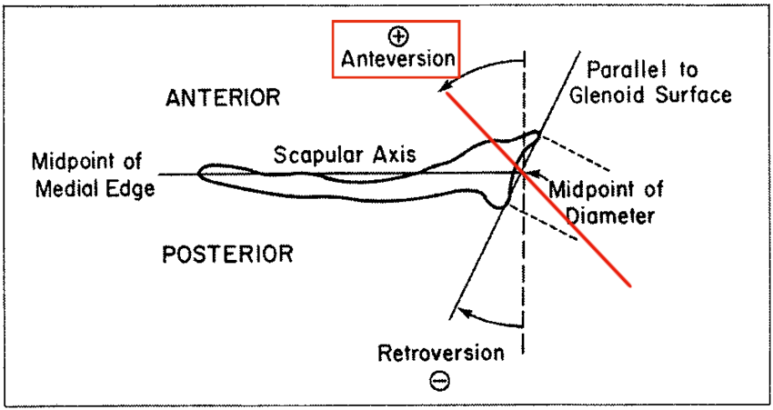

견갑골의 각도는 몸의 중심선(Coronal plane=frontal plane)으로부터 30 ~ 35도 기울어져 있고, 늑골에 거의 바짝 붙어있는것이 정상입니다.

과도한 어깨 앞으로 빠짐상태인 전인 상태가 유지되고, 후인은 잘 되지않게되면 견관절의 관절와(Glenoid)에 해부학적문제가 아닌 기능적인 앞쪽기울어짐(fuctional anteversion)이 발생되면서 관절와순(Glenoid labrum)에 상완골두가 잘 밀착되지 않고 붕 뜨게 되면서 앞쪽 어깨의 안정성이 떨어지면서 손상에 취약하게 됩니다. 이는 결국 어깨 전방 탈구(Anterior dislocation, 어깨 탈구의 95% 차지, https://www.youtube.com/watch?v=xDePRKeB4kc)가 더 쉽게 발생할 수 있게됩니다.